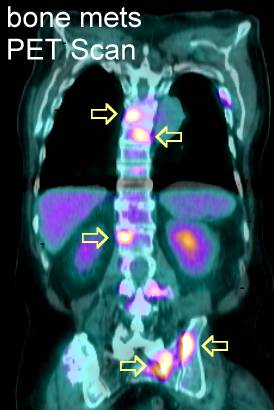

PET Scans of Bone Metastases

PET scans may show these lesions best (go here , here, here, here, here, here, here , here , here , here , here , here , here and here) even better than CT scans (go here , here, here and here) and better than MRI (here). PET scans also show the response to radiation (go here). PET is helpful for hard to see areas like the ribs or scapula. PET's may be best for

osteolytic lesions and bone scans best for blastic metastases (go

here). |